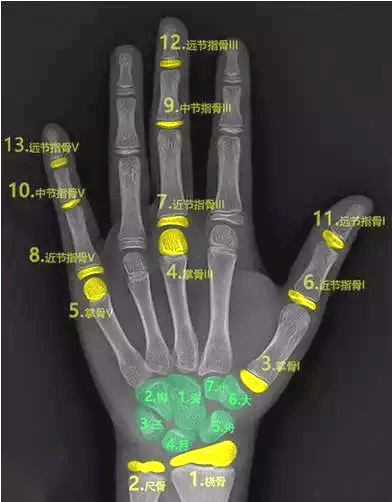

三、骨龄测试法

骨龄是骨骼年龄的简称,比实际年龄更能反映人体骨骼的成熟度。

一般是拍摄左手腕部的X线片,观察指骨、腕骨、桡骨、尺骨下端的骨化中心出现的时间、面积大小、判断骨骼实际发育程度,来确定骨龄。

如果骨龄小于生活年龄1岁以上,提示有生长激素缺乏症的可能;骨龄大于生活年龄1岁以上的孩子可能早熟,往往其成年的最终身高反而受损。

因此骨龄异常需要尽早到专业医疗机构就诊,必要时进行医学干预和药物治疗。